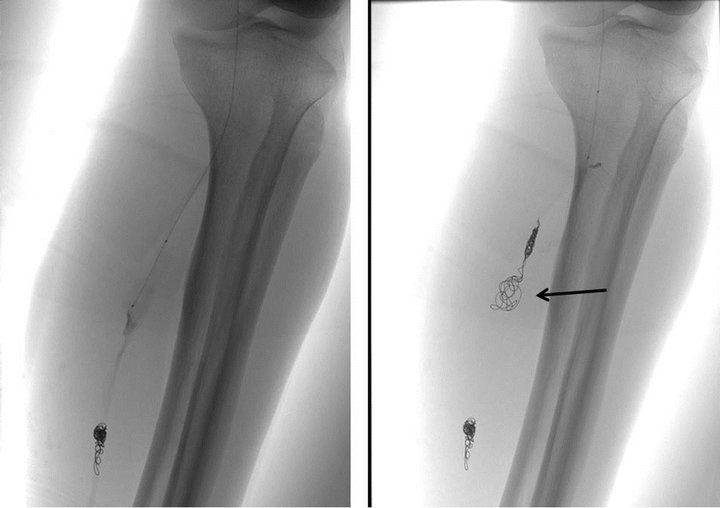

Left superficial femoral arteriogram showed a fusiform aneurysm of the posterior tibial artery with a segmental wall irregularity distal to the aneurysm (Figure 3(a)). Late arterial phase of the arteriogram also revealed an extravasation from the aneurysm (Figure 3(b)). Because we could easily pass the catheter through the aneurysm and irregular segment using microcatheter system (Renegade-18, Boston Scientific Japan, Tokyo, Japan/0.016-inch Radifocus GT wire, Terumo, Tokyo, Japan), we planned an internal trapping of the abnormal segment by the distal-to-proximal fashion. We initially deployed three detachable coils (Orbit Galaxy 5.0 mm - 15 cm, 4.0 mm - 12 cm, 4.0 mm - 12 cm, Johnson and Johnson, Tokyo, Japan) at the distal end of the irregular segment. Then we added a detachable coil (Matrix2 8.0 mm - 30 cm, Boston Scientific Japan, Tokyo, Japan) within the aneurysm followed by three coils (Matrix2 5.0 mm - 15 cm, Orbit Galaxy 3.5 mm - 7.5 cm, 3.5 mm - 7.5 cm) deployed at just proximal to the aneurysm (Figure 4).

Figure 4. Left: Posterior tibial arteriogram during the endovascular procedure shows three detachable coils deployed at the distal end of irregular segment. Microcatheter tip is positioned within the proximal fusiform aneurysm. Right: Digital radiogram reveals a complete internal trapping by detachable coils. Rough coiling indicates the fusiform aneurysm (arrow).